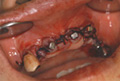

Q 実際にT-typeを臨床に用いられた症例における感想をお聞かせください。

また抜歯即時症例にも数例適応しましたが、すべて良好な経過をたどっています。 通常の症例にもT-typeは対応することが可能だと考えますが、フィクスチャー12?のものがあればさらに適応症例が広がると考えています。